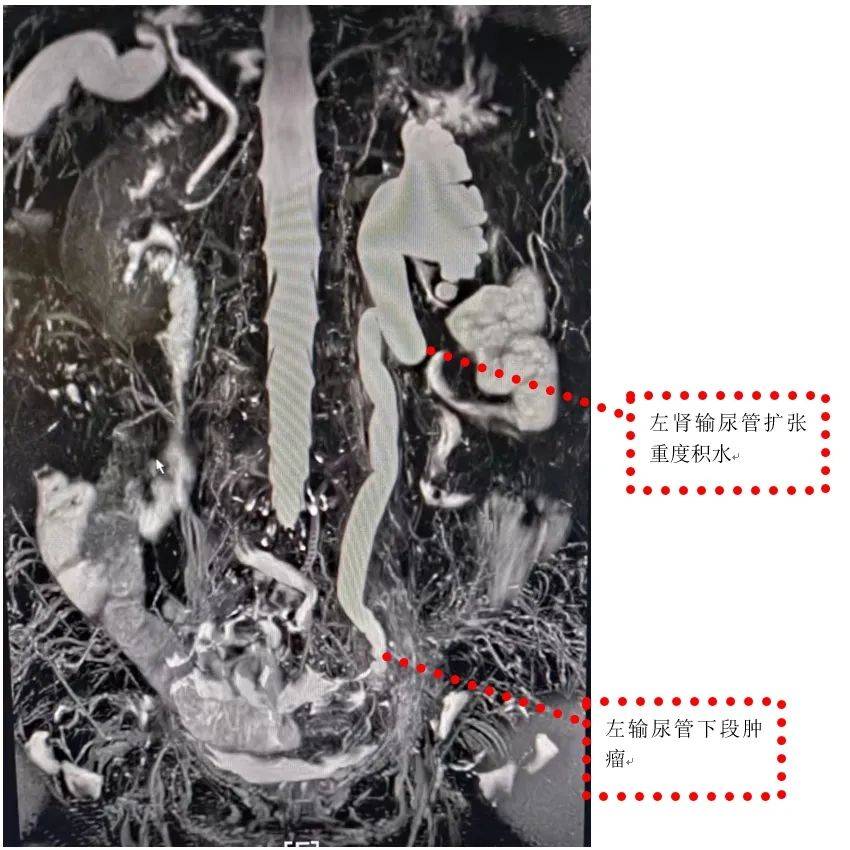

输尿管丨左侧输尿管乳头状癌

图片尺寸1080x608![【共享】输尿管癌照片 [病例帖]](https://i.ecywang.com/upload/1/img2.baidu.com/it/u=3737601943,2848469263&fm=253&fmt=auto&app=138&f=JPEG?w=667&h=500)